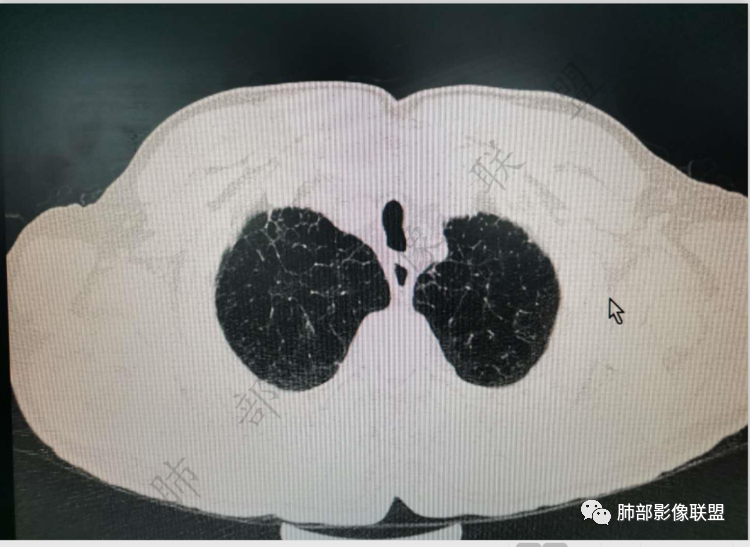

肺气肿背景

支气管变形、壁增厚,提示慢性支气管炎症

边缘平直

宽基底与胸膜相连,附近胸膜增厚,糊墙

内乳动脉关系似乎不密切

内部有低强化区,边界尚清

还是支持炎性放前面,恶性待排